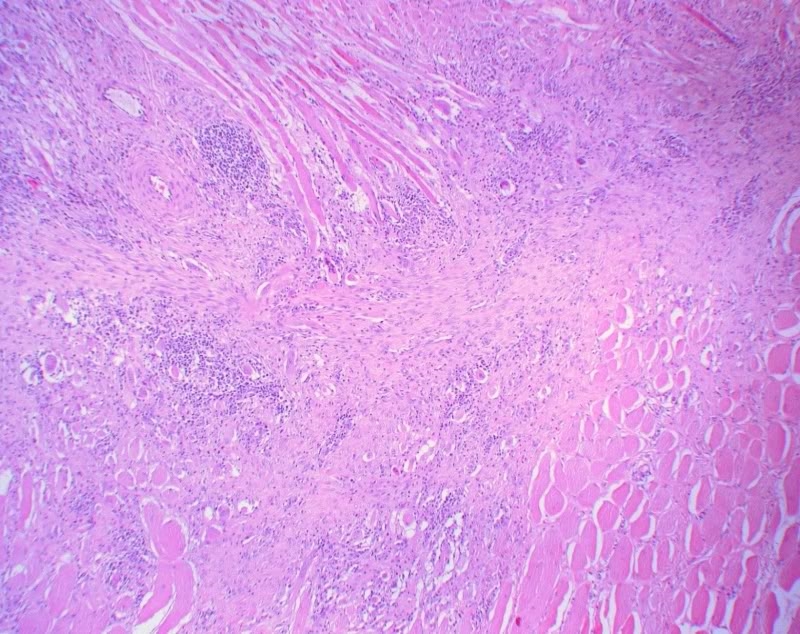

Die Narbe liegt hier tief unter der Haut, nämlich in der Muskulatur der Bauchwand, die man am oberen und unteren Bildrand erkennen kann. Zentral liegt die Narbe, die aus hellen Kollagenfasern und in diesem Falle noch recht vielen Fibroblasten aufgebaut ist. Im Randbereich der Narbe erkennt man reichlich Lymphozyten und Plasmazellen, ein chronisch-entzündliches Infiltrat. Ferner sieht man im oberen rechten Quadranten sowie am linken Bildrand Fremkörperriesenzellen; diese liegen am Rand von chirurgischem Nahmaterial, das hier nicht erkennbar ist.

Eine Narbe ist das Endprodukt verschiedener Entzündungsreaktionen, an der Haut i.d.R. der Wundheilung. Narben gibt es aber auch z.B. im Herzmuskel oder in abgewandelter Form in verschiedenen inneren Organen, ja sogar im Gehirn. Eine Narbe ist typischerweise aus zellarmem und faserreichem Kollagengewebe aufgebaut.